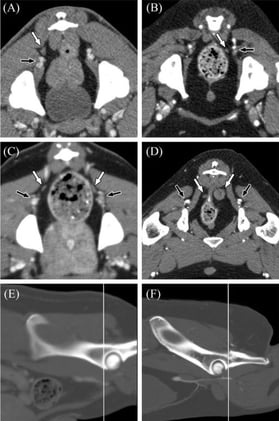

- Anatomy

Anatomy